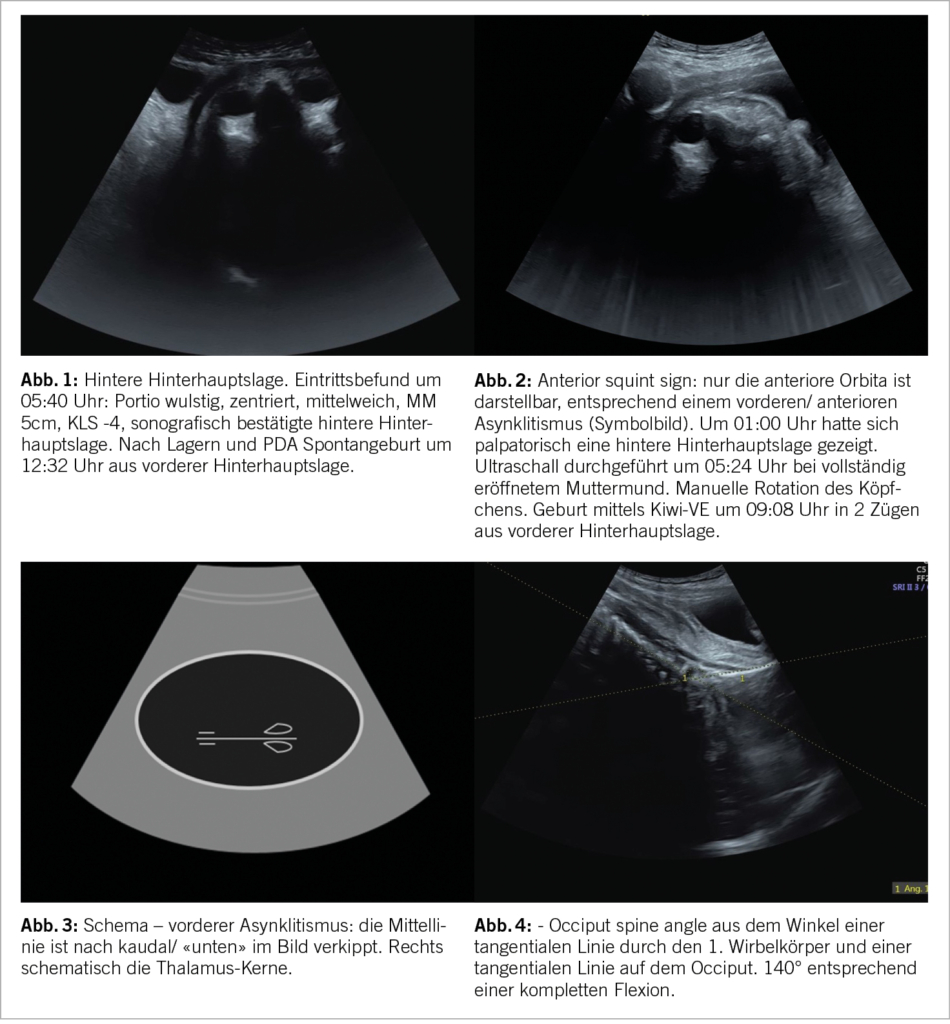

Der Ultraschallkopf wird suprasymphysär aufgesetzt. Mit einem Transversalschnitt lassen sich (nach weiter kranial gewinkelt) die Wirbelsäule und damit die Stellung, weiter nach unten gewinkelt der Kopf im Transversalschnitt darstellen. Dies ermöglicht eine Beurteilung der Einstellung (Abb. 1).

Dabei sollte auch auf Falx, Thalamus und die Orbitae geachtet werden: mit diesem Zugang ist die Beurteilung einer Scheitelbeineinstellung möglich (Abb. 3). Malvasi et al. beschreiben zur Detektion eines Asynklitismus das «squint sign» («Schiel-Zeichen», Abb. 2) und das «thalamic sunset sign» (3, 4), ausserdem ist die Falx im Falle eines Asynklitismus nach kaudal (vorderer Asynklitismus) bzw. kranial (hinterer Asynklitismus) verschoben.

Mittels eines suprasymphysären sagittalen Schnitts lassen sich mütterliche Blase und Symphyse sowie kindlicher Kopf und, ggf. paramedian, noch die fetale Wirbelsäule – oder aber Gesicht – darstellen (Abb. 4).

Ghi et al. prägten 2016 den Begriff «Occiput-Spine-Angle» zur Diagnose einer Deflexionshaltung (5).

Hierbei wird eine Linie tangential durch das Occiput und tangential durch den ersten Wirbelkörper gelegt.

In einer Multicenter-Bestätigungsstudie legten die Autoren den cut-off von 109° fest, unterhalb dessen ein Kaiserschnitt wahrscheinlicher war als bei einem Winkel >109° (6). Auch bei einer occipito-posterioren Einstellung war die sonografische Bestimmung der (De)Flexion möglich mittels des chin-to-chest-angles.